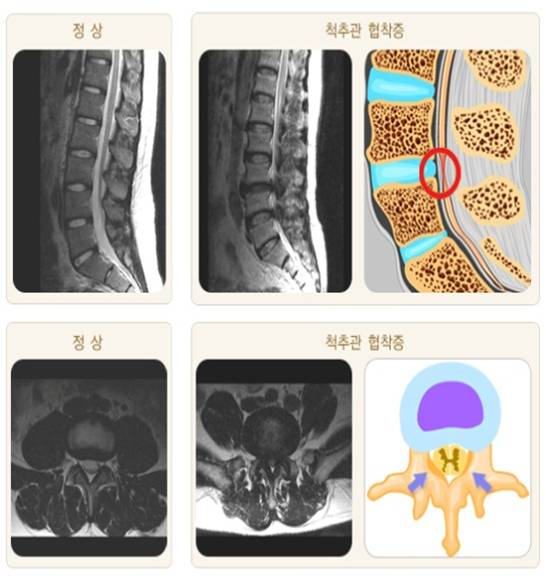

- 척추관협착증: 척추관이 좁아져 신경을 압박하는 상태로, 주로 노화로 인한 퇴행성 변화나 후종인대골화증, 외상 등에 의해 발생합니다. 척추관협착증은 주로 허리나 목 부위에서 발생하며, 신경 압박으로 인해 다양한 증상을 유발할 수 있습니다.

척추관협착증 척추관협착증의 주요 원인에는 여러 가지가 있습니다.

- 퇴행성 변화: 나이가 들면서 척추 디스크가 탈수되고 퇴행하면서 높이가 줄어들고, 척추뼈와 인대가 두꺼워져 척추관이 좁아집니다.

- 후종인대골화증: 척추의 후종인대가 비정상적으로 두꺼워지거나 석회화되면 척추관이 좁아질 수 있습니다.

- 척추분리증: 척추뼈가 비정상적으로 움직이거나 분리되면 척추관이 좁아질 수 있습니다.

- 선천적 기형: 선천적으로 척추관이 좁은 사람들은 나이가 들면서 척추관협착증이 발생할 가능성이 높아집니다.

- 외상: 척추에 외상이 발생하면 척추관이 좁아질 수 있습니다.